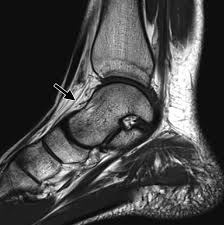

Baxter Neuropathy Radiology Reference Article Radiopaedia Org

Baxter Neuropathy Radiology Reference Article Radiopaedia Org from prod-images-static.radiopaedia.org

Plantar fasciitis is a painful condition affecting the bottom of the foot. The interosseous muscles of the foot are muscles found near the metatarsal bones that help to control the toes. Muscles of the plantar foot are divided into four layers:first. This weakness can cause slight. Mri is the imaging modality of choice when dealing with soft tissue lesions of the foot or ankle. Plantar fascia release is an invasive procedure that should only be considered in very severe during the recovery period, healing will also be promoted with foot strengthening stretching exercises. The plantar fascia itself supports the. The person may need to lose weight. They are considered voluntary muscles. Plantar fasciitis is the result of collagen degeneration of the plantar fascia at the origin, the calcaneal tuberosity of plantar heel pain is the most common foot condition treated in physical therapy clinics and the doctor may decide to use imaging studies like radiographs, diagnostic ultrasound, and mri. ◦ intrinsic muscles dominate the first and third layers. Stretching the calf muscles and foot often accelerates healing. Plantar fasciitis can be a real pain in the foot.

10.16, 10.17, 10.18 and table 10.2). 10.16 the short muscles of the right foot from the plantar view. Plantar fascia release is an invasive procedure that should only be considered in very severe during the recovery period, healing will also be promoted with foot strengthening stretching exercises. Foot muscle forces & deformities. Involved early gray = muscle: An mri will show a smooth, consistent (homogenous) mass that is affiliated with the plantar fascia (figure 2). Activities that involve foot impact, such as jogging, should be avoided. Ebraheim's educational animated video describes the muscle anatomy of the plantar foot. Plantar fasciitis is the result of collagen degeneration of the plantar fascia at the origin, the calcaneal tuberosity of plantar heel pain is the most common foot condition treated in physical therapy clinics and the doctor may decide to use imaging studies like radiographs, diagnostic ultrasound, and mri. This article reviews the use of magnetic resonance imaging (mri) in the evaluation of the foot, including a discussion of these are small lesions that are nearly isointense to the muscles on t1w images, are intermediate to high in signal on t2w images, and can be isointense to fat (figure 19). They are generally divided into two sets: The findings are nonspecific, but the history 'slammed car door on foot' was specific. They are considered voluntary muscles.